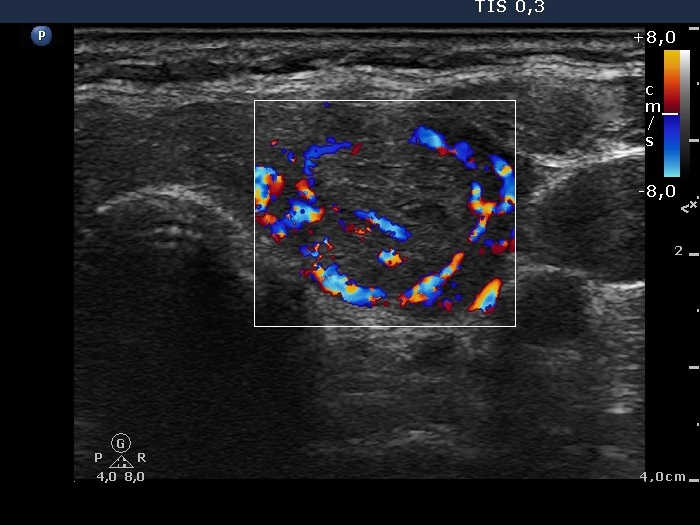

Graves' disease - case 1147 (ultrasonographic picture 7)

Right lobe, longitudinal scan

Left lobe, transverse scan, color Doppler mode. The vascularization is increased. The nodule displays perinodular blood flow.